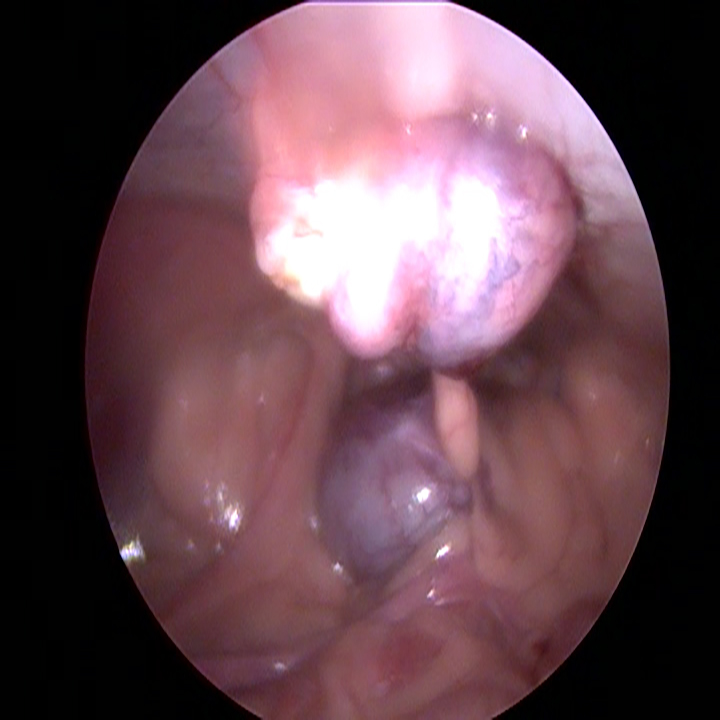

Wanneer alle trocars geplaatst zijn, kantelen we de operatietafel naar voren en leggen we de patiënt op haar zij. Dan gaan we op zoek naar de linker eierstok. Doordat de milt eroverheen ligt kan dit soms wat meer moeite kosten. Eenmaal gevonden, branden we de ophangbanden en bloedvaten van het ovarium door. Hierbij moet ervoor gezorgd worden dat er ver genoeg van de nieren en de buikwand af gewerkt wordt, om hitteschade te voorkomen. De eierstok wordt via het gat bij het bekken verwijderd. Na het controleren van de plek waar de eierstok verwijderd is en na het opnieuw plaatsten van de achterste trocar, wordt de andere kant gedaan.

Vervolgens wordt de hond weer recht gelegd en worden de trocars verwijderd. De CO2 wordt uit de buik verwijderd. De gaatjes worden elk afzonderlijk in 3 laagjes gesloten.

De daadwerkelijke laparoscopische sterilisatie, in beeld: